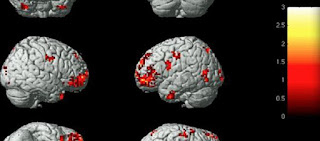

أما الحسد فقد لاحظ العلماء أنه يؤذي الدماغ ويسبب اضطرابات في الشخصية ويكون الدماغ في حالة الحسد مشوشاً ويصعب على العلماء تمييز مناطق الحسد.

بعد تجارب طويلة على الدماغ البشري تبين للعلماء ومن خلال أجهزة المسح بالرنين المغنطيسي أن الدماغ يكون في حالة فوضى أثناء الحسد، ولذلك يقول العلماء إن الحسد عادة سيئة ومضرة بالدماغ.